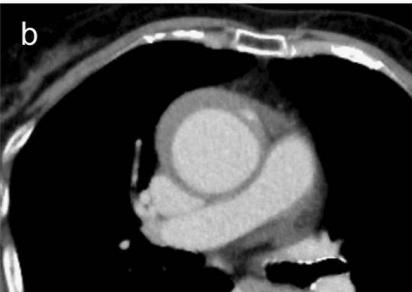

下图的胸部CT平扫,有什么致命的问题?

图7

仔细一看,主动脉里面有线样阴影!并且,线样阴影两边的密度一高一低!

图8

增强CT一看,主动脉夹层,密度相对高的是流动的血液!

图9